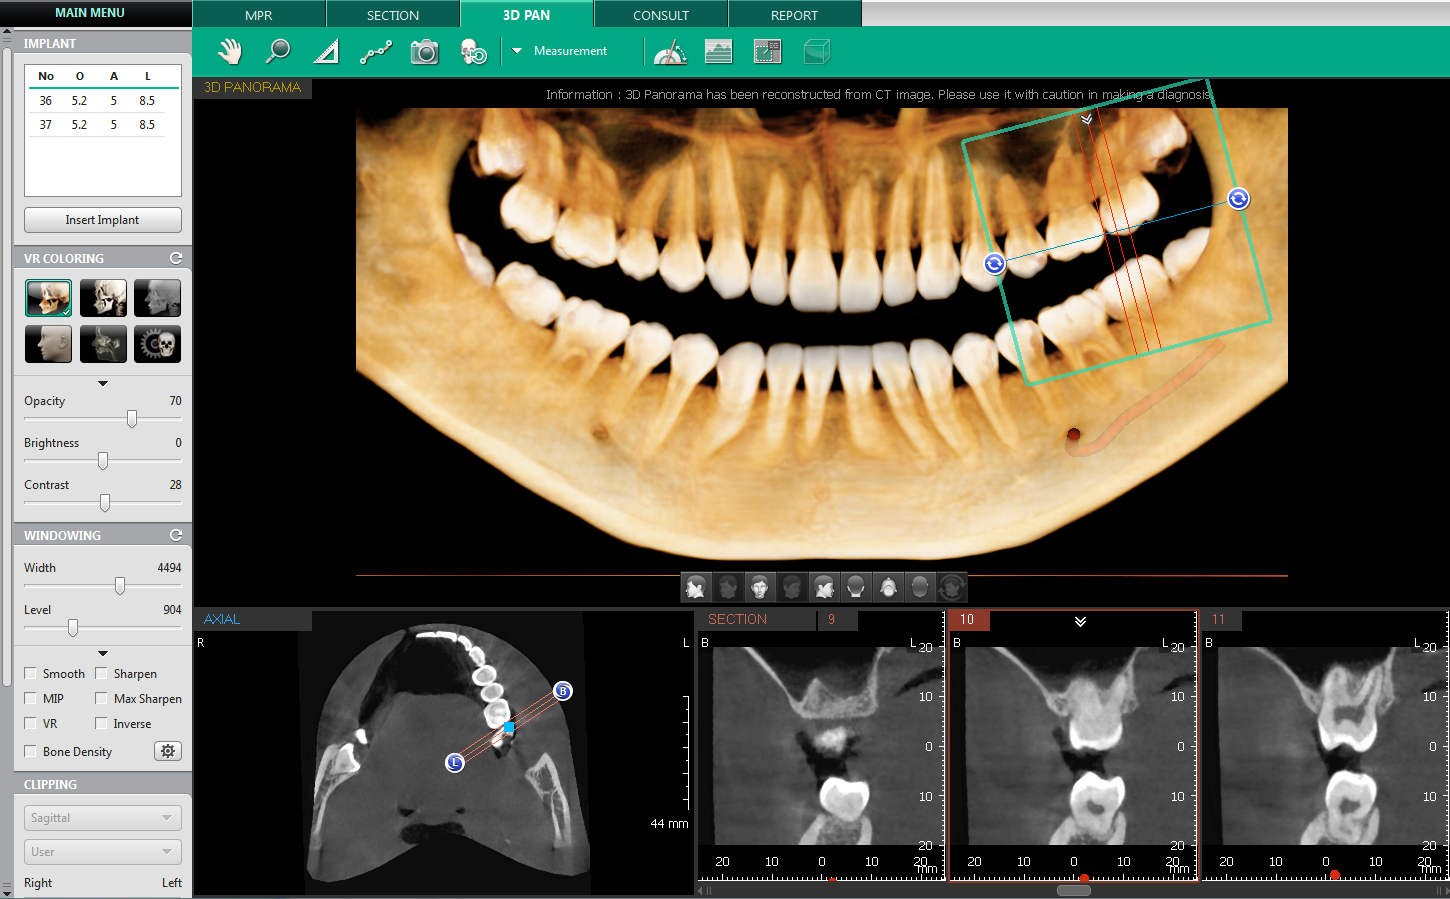

• - оценка топографии корней зубов (Рис.2).

Рис.2 Программное обеспечение Ez3D-i V4.3.0 от Vatech. Дентальная объемная томограмма ортодонтического пациента.

В ортодонтии:

• - планирование лечения сложной зубочелюстной патологии, аномалии прикуса, устранение врожденных аномалий челюстно-лицевой области;

• - диагностика состояния импактных зубов;